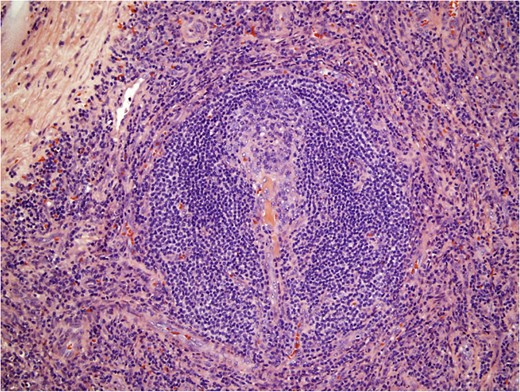

Histological examination (Fig. 3) diagnosed an accessory spleen with unicentric Castleman’s disease (UCD) hyaline vascular variant (7.7 × 6.0 × 5.8 cm3) without pathologic changes to the attached lymph node (2.2 × 2.3 × 2.0 cm3) or the encased adrenal gland (5.5 × 1.5 × 0.8 cm3). A blood panel revealed no evidence of leukemia or lymphoma. The patient was seen for follow-up 1 week postsurgery and reported no pain or discomfort. She will continue to be monitored with physical examinations, scans and serum tumor markers.

Histological pathology of Castleman’s disease, hyaline vascular variant. Involuted follicular germinal center penetrated by hyalinized small vessels and surrounded by concentric ‘onion rings’ of mantle zone lymphocytes.

UCD is not associated with infections or malignancies. It is more common than MCD; 72% of CD cases are UCD hyaline vascular variant [3]. UCD distributes in the thorax (30%), neck (23%), abdomen (20%), retroperitoneum (17%), axilla (5%), groin (3%) and pelvis (2%) [6]. Here, we present UCD hyaline vascular variant arising in an accessory spleen. An accessory spleen is a congenital development of splenic tissue away from the spleen occurring in 16% of the population [7]. Our patient’s lesion was discovered accidentally when she came in for an ultrasound after complaining of abdominal pain with pressure. The mass’s heterogeneous composition was most likely due to its substantial size as small UCD tumors are homogeneous [3]. EUS-FNA revealed interfollicular hypervascularity and polymorphous proliferation of small lymphocytes, histiocytes, eosinophils and plasma cells, suggestive of UCD mixed with splenic tissue. It should be emphasized that confirmation of UCD is possible only upon postoperative examination. Imaging can suggest UCD and be used to rule out MCD. However, UCD resembles other tumors on imaging. Preoperative cytology can indicate UCD but cannot exclude reactive lymphadenopathy and other lymphoproliferative disorders. Final pathology confirmed features indicative of UCD hyaline vascular variant on a background of splenic tissue: involuted follicular germinal centers predominated by dendritic cells, concentric rings of mantle zone lymphocytes and penetrating hyalinized small vessels. Following resection, a precautionary leukemia/lymphoma panel was performed and yielded negative results.